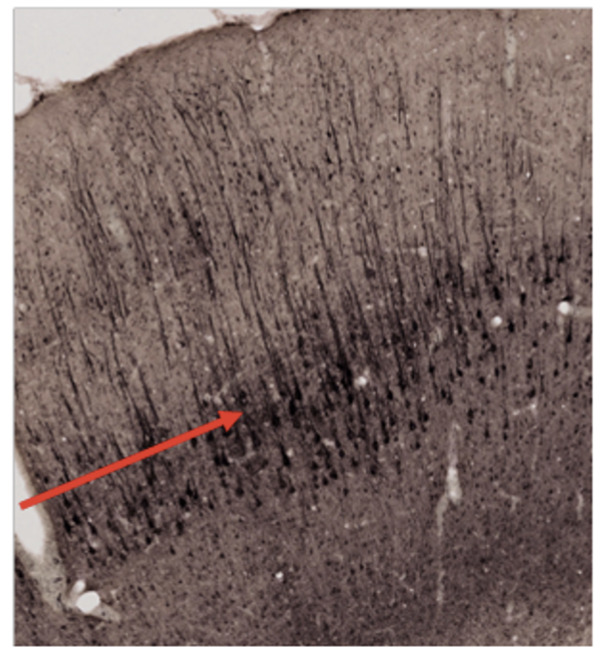

Vilket cellager pekar pilen på? (1p)

Välj ett alternativ:

- A: Lamina granularis externa

- B: Lamina pyramidalis interna

- C: Lamina pyramidalis externa

- D: Lamina molekularis

- E: Purkinjecellslagret

- F: Lamina granularis interna

- G: Lamina multiforme